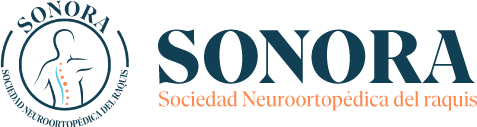

La escoliosis es una deformidad rotacional de la columna vertebral, que se proyecta en los tres planos del espacio: coronal ,sagital y axial. Cuando hablamos de escoliosis debemos diferenciar según su edad de aparición entre escoliosis infantiles, juveniles y del adulto.

El tratamiento abarca desde la observación periódica con radiografías de control, el uso de corsés y ortesis correctoras, ejercicios dirigidos, hasta la cirugía.

Conseguir una correcta alineación del raquis puede llegar a necesitar cirugía. La cirugía tiene dos metas principales: detener el avance de la curva y corregir la deformidad espinal.

La cirugía en las llamadas idiopática del adolescente se indica para los casos de escoliosis de más de 40°, o para pacientes que no responden al corsé. La cirugía generalmente tiene dos metas principales: detener el avance de la curva y corregir la deformidad espinal.